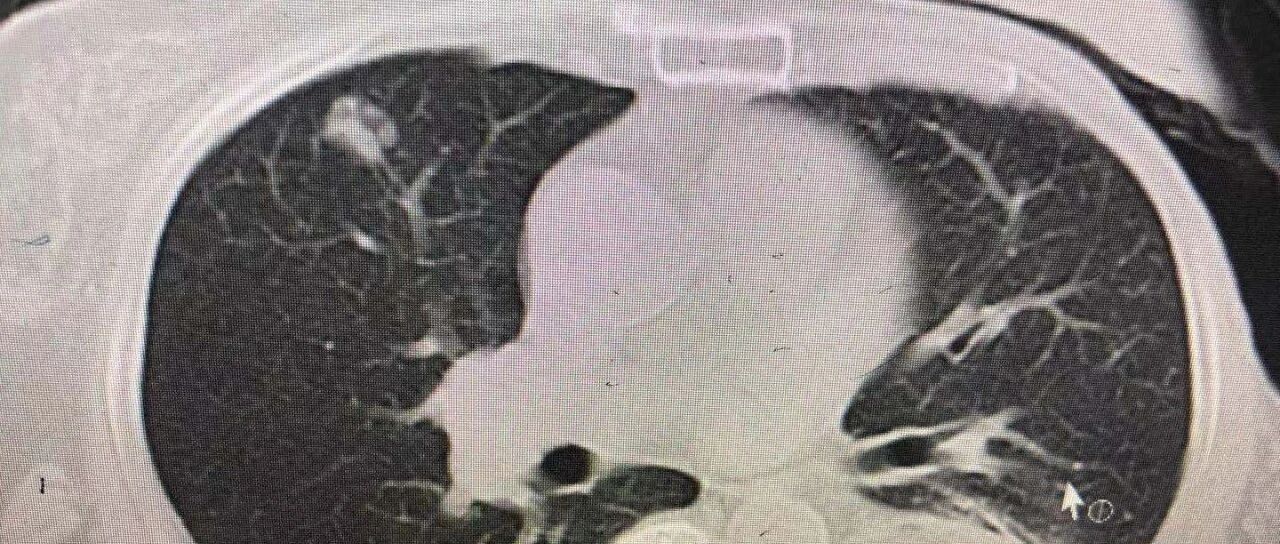

定期复查包括血尿常规、肝肾功能、肿瘤标志物及相关影像学检查,有个很大的目的就是做到及早发现病灶的端倪、早治疗。